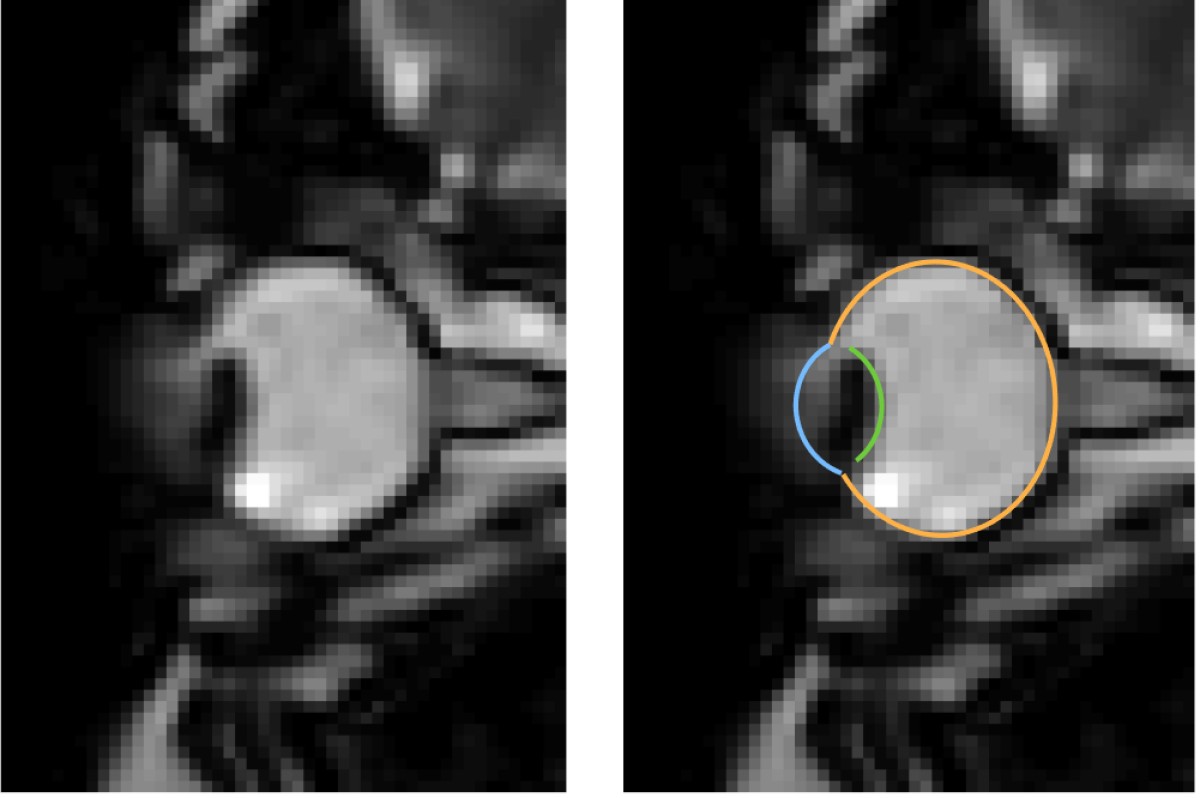

MRT-Aufnahmen von Augenbewegungen beim Blinzeln: Das Auge wird in die Augenhöhle zurückgezogen. Das linke Bild zeigt jeweils nur die dynamischen MRT-Daten, das rechte zusätzlich dazu die Segmentierung des Auges durch den MREyeTrack. Die Fotostecke bestehend aus sechs Bildern stellt die Augenbewegung dar.© WWU - Johannes Kirchner

Augenbewegungen werden typischerweise mit sogenannten Eyetrackern gemessen, also Hochgeschwindigkeitskameras, die die Position der Pupille filmen. Einige Aspekte von Augenbewegungen lassen sich damit jedoch nicht messen. „Es ist uns gelungen, ein Verfahren zu entwickeln, das Augenbewegungen in bisher unerreichter zeitlicher Auflösung mit Echtzeit-MRT-Sequenzen misst. So konnten wir mit unserer Methode zum Beispiel zeigen, dass der komplette Augapfel beim Blinzeln in die Augenhöhle zurückgezogen wird“, erläutert Autor Johannes Kirchner, wissenschaftlicher Mitarbeiter am Institut für Psychologie der WWU. Die Methode haben die WWU-Wissenschaftler mit der Co-Autorin Prof. Dr. Tamara Watson von der Western Sydney University entwickelt.

MRT ist ein relativ langsames Verfahren, die zeitliche Auflösung bewegt sich normalerweise im Bereich von Sekunden oder Minuten. Augenbewegung hingegen sind schnell und dauern typischerweise nur ein paar Dutzend Millisekunden an. Entwicklungen in den vergangenen zehn Jahren haben es jedoch ermöglicht, 2-D-MRT-Aufnahmen mit bis zu 20 Millisekunden zeitlicher Auflösung zu produzieren. Diese ultraschnellen Verfahren kommen vor allem bei der Herzbildgebung zum Einsatz und werden bislang nicht auf die Messung von Augenbewegungen angewandt. „In unseren Aufnahmen haben wir eine zeitliche Auflösung von etwa 35 Millisekunden erzielt. Da bei einer gesamten Messzeit von ein paar Minuten mehr als 10.000 Bilder entstehen, braucht man, um tatsächliches Eyetracking zu betreiben, einen vollautomatischen Algorithmus, um diese Daten auszuwerten“, schildert Mitautor Prof. Dr. Markus Lappe, Leiter des Lehrstuhls für Allgemeine Psychologie und kognitive Neurowissenschaften am Institut für Psychologie der WWU. „Mit ‚MREyeTrack’ haben wir einen solchen sogenannten Segmentierungsalgorithmus entwickelt, der es erstmals ermöglicht, vollautomatisch Position und Orientierung des Auges in jedem einzelnen Bild zu analysieren.“